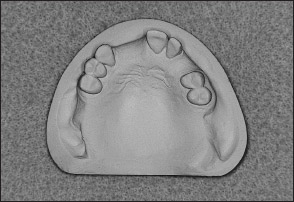

• Kennedy Class I arch: Characterized by bilateral edentulous areas located posterior to the remaining natural teeth (Figs 1-11 and 1-12).

Fig 1-11 Maxillary Kennedy Class I arch.

Fig 1-12 Mandibular Kennedy Class I arch.